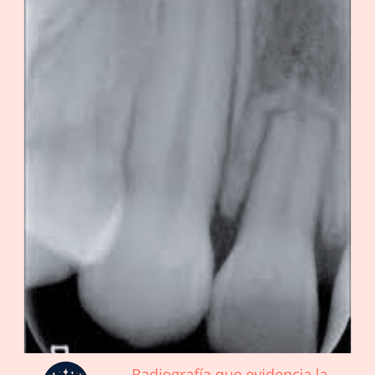

Radiografías: Se toman radiografías para visualizar el grado de reabsorción en la raíz del diente. En algunos casos, puede ser necesaria una tomografía computarizada (CBCT) para obtener imágenes más detalladas.

Resultados esperados: Si la reabsorción es leve, el diente puede ser tratado con endodoncia. Si es extensa, puede ser necesario extraer el diente.